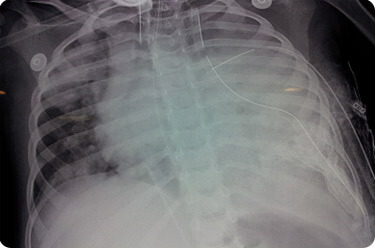

ECMO Cannulas with ICD